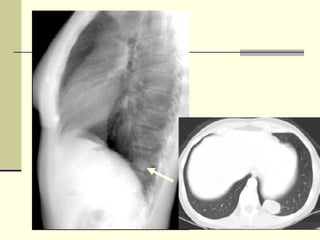

CONSOLIDATION Density in left lower lung field  Loss of left heart silhouette  Diaphragmatic silhouette intact  No shift of mediastinum  Blunting of costophrenic angle

CONSOLIDATION Density inleft lower lung field Loss of left heart silhouette Diaphragmatic silhouette intact No shift of mediastinum Blunting of costophrenic angle